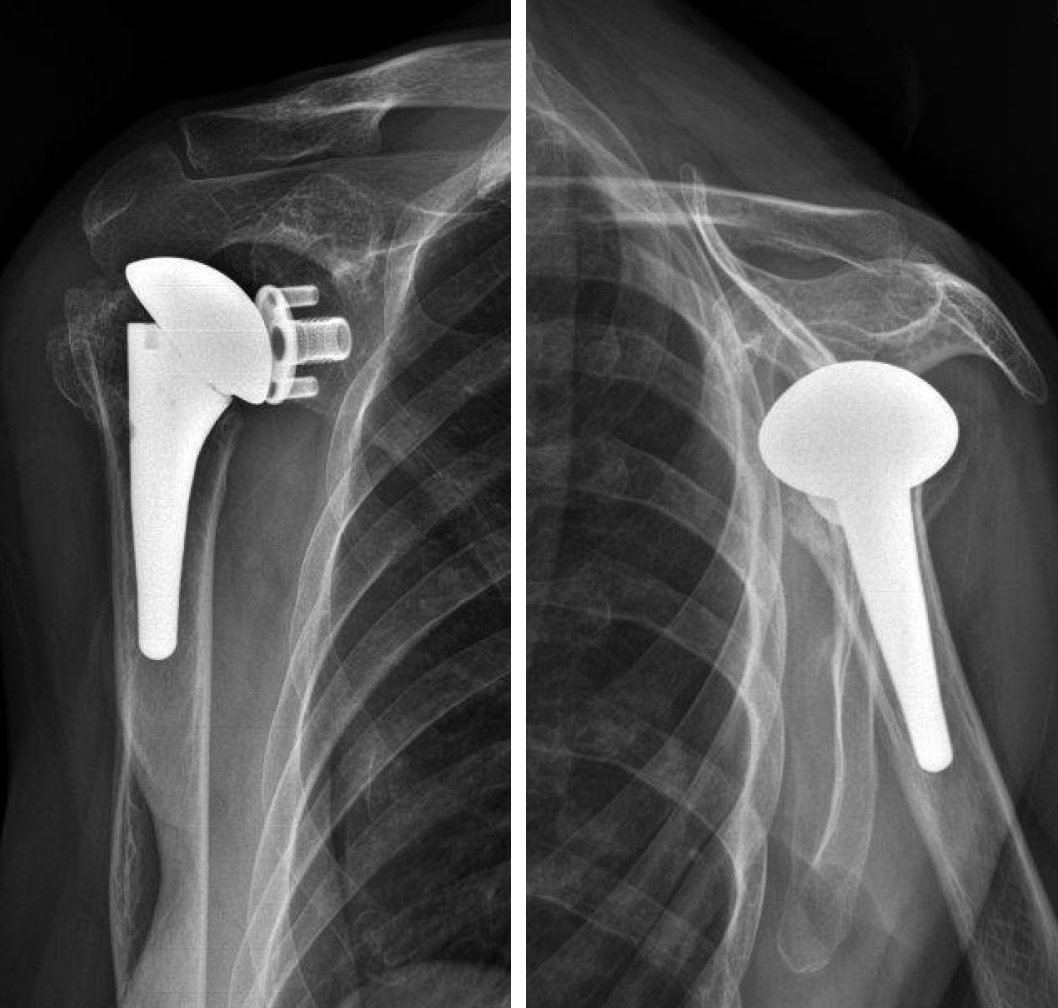

1 year follow up

- No complications

- No pain

- Good ROM